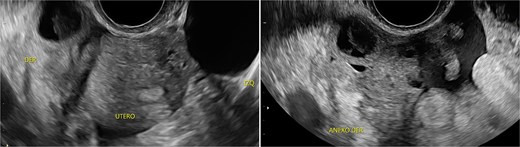

Stage III pelvic inflammatory disease (PID) was suspected based on ultrasound (Figs 1–3) and gynecological examination, which revealed mild bulging of the right lateral fornix, cervical motion tenderness, and a white, non-foul-smelling vaginal discharge. Empiric intravenous antibiotic therapy was initiated, followed by exploratory laparotomy via a Pfannenstiel incision. Intraoperative findings included an 8 × 5 cm uterus, edematous fallopian tubes, and a simple 5 × 5 cm left adnexal cyst. Cystectomy was performed.

Sagittal transvaginal ultrasound showing free fluid in the uterine fundus.

Transverse transvaginal ultrasound demonstrating a 4.7 cm bilocular cyst in the left ovary and a dominant follicle in the right ovary, with moderate periovarian fluid adjacent to the right ovary.

The cervical motion tenderness—a minimum diagnostic criterion—along with fever and elevated CRP, led to a misdiagnosis of PID, with the ultrasound mass interpreted as a tubo-ovarian complex. Retrospectively, both low-normal hemoglobin and absence of mucopurulent cervical discharge were notable. When mucopurulent discharge and leukocytes on vaginal wet prep are absent, PID is unlikely, and alternative diagnoses should be considered [6].

IMTs lack distinctive imaging characteristics. Ultrasound often shows increased vascularity. Contrast-enhanced computed tomography is the imaging modality of choice for gastrointestinal IMTs, which typically present as hypodense, heterogeneous, well-defined masses frequently mistaken for colorectal carcinoma [7].